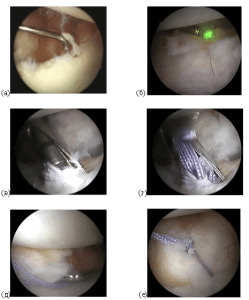

Основываясь на комплексном обследовании пациента мы применяем ту или иную хирургическую методику лечения нестабильности плечевого сустава (привычного вывиха). На настоящий момент наиболее широкое применение имеют 2 типа операций: артроскопия плечевого сустава и артроскопическое восстановление капсульно-связочного аппарата (повреждение Банкарта) при помощи якорных фиксаторов и костно-пластическая операция Латарже. В случае отсутствия значительного костного дефекта суставного отростка лопатки выполняется артроскопия плечевого сустава и стабилизация — восстановление повреждения Банкарта.

Рисунок: Интраоперационные фото артроскопического восстановления повреждения Банкарта при помощи якорных фиксаторов.

Операция практически не сопровождается осложнениями. Выполняется миниинвазивно через 2-3 кожных прокола. Стабилизирующий эффект операции можно дополнять обработкой передней капсулы при помощи гольмиевого лазера, что приводит к увеличению прочности капсульно-связочных структур. Больной может быть уже выписан на 2-3 сутки после операции на амбулаторное долечивание. Срок реабилитации после артроскопического восстановления повреждения Банкарта занимает 6-8 мес.

В случае наличия сопутствующего повреждения Хилл-Сакса выполняем манипуляцию «реимплиссаж», когда в зону дефекта фиксируется сухожилие подостной мышцы.

Рисунок: Артроскопия плечевого сустава: Этапы процедуры «ремплиссаж».